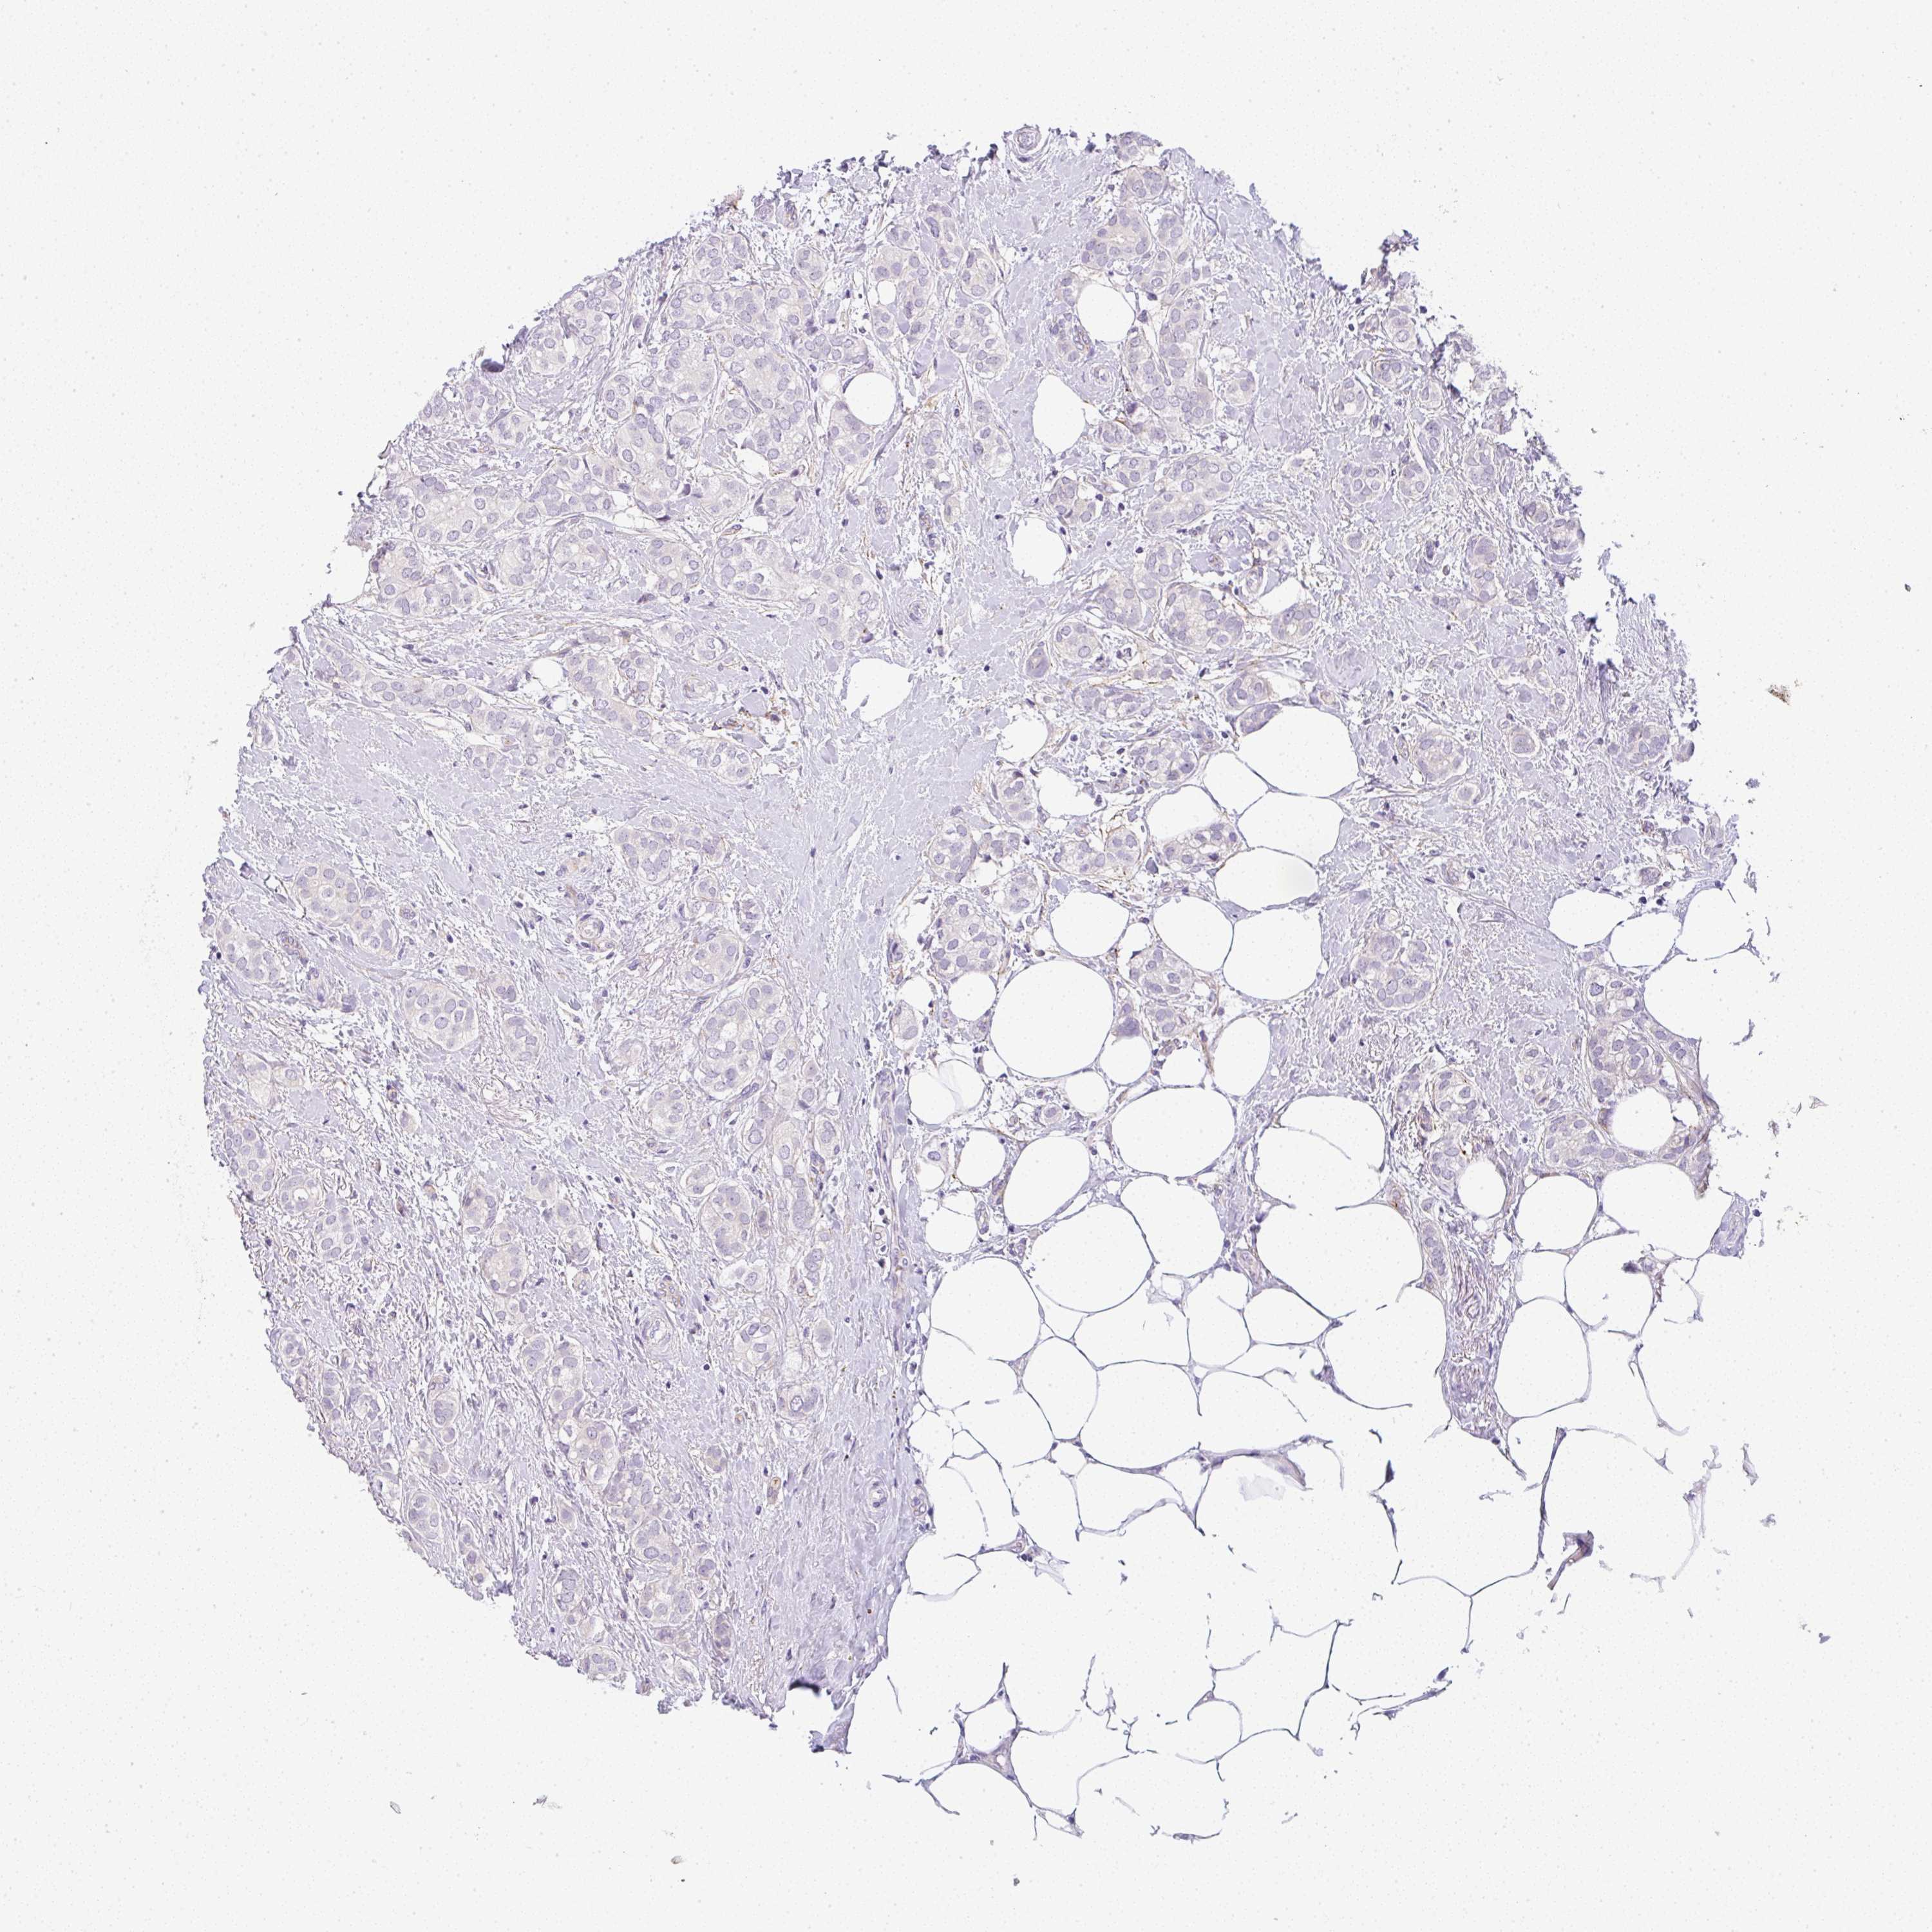

BRCA TCGA BRCA VALIDATION PROTEIN EXPRESSION

ANTIBODIES

AND

VALIDATION